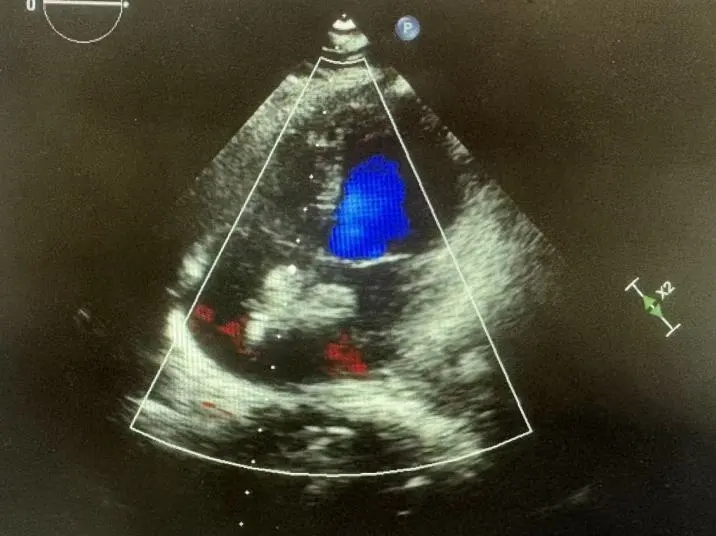

彩色多普勒血流成像显示无残余分流存在

超声下可见封堵器形态良好,封堵成功

封堵成功

封堵器位置正确、形态良好